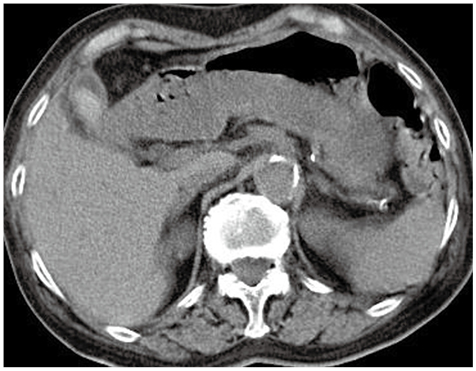

症例2

症例2の患者情報

80歳代,女性。

悪性リンパ腫治療中に発症した誤嚥性肺炎に対し,セフトリアキソン(CTRX)投与後。

腹部症状はなし。